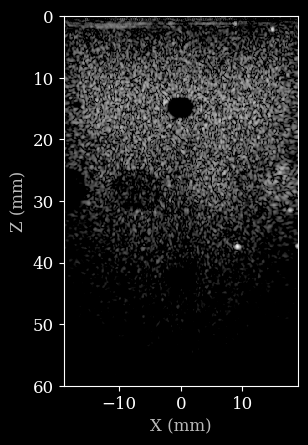

First, we will use a default pipeline to process the data, and reconstruct the B-mode image from raw data. Note that the data as well as the parameters are passed along together as a dictionary to the pipeline. By default, the data will be assumed to be stored in the data key of the dictionary. Parameters are stored under their own name. This can all be customized, but for now we will use the defaults.

[7]:

plot_data(image, dynamic_range, scan)

../../_images/notebooks_pipeline_zea_pipeline_example_14_1.png

Now let’s construct a custom pipeline to process the data. We will use the zea.Pipeline class and pass a list of operations to it. The operations will be executed in the order they are provided, and the output of each operation will be passed as input to the next operation as a dictionary. You can specify the input and output key for each operation, which for will be assumed to be data by default. This also allows you to create complex branched pipelines, but we will keep it simple for now. Note that pipelines can also be nested, which we will do for the beamforming stage. This allows us to use the zea.ops.PatchedGrid pipeline to wrap the beamforming operations, resulting in a more memory efficient pipeline.

../../_images/notebooks_pipeline_zea_pipeline_example_16_1.png